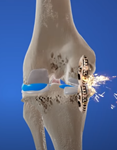

主要頸源性頭暈、頭痛的成因: (1)上頸椎神經受壓:

因為頸椎分為上頸椎和下頸椎,頸椎C3節為分介線,C3以上椎節為上頸椎節,C3以下椎節為下頸椎節。凡是上頸椎神經受壓,例如:椎間盤突出、椎孔狹窄、椎體移位或下陷,都會有機會導致前額痛、後枕痛、眼窩痛、上頸椎痛。

椎間盤突出

椎間盤回縮